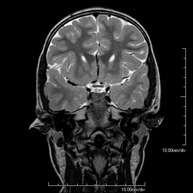

- RM Cerebral (craneal)

Prueba diagnóstica no invasiva que consiste en la obtención de imágenes de alta definición anatómica del cerebro mediante el empleo de un campo electromagnético y ondas de radio (con un emisor y un receptor). No utiliza radiación ionizante. Indicaciones: problemas vasculares, pérdida de memoria, epilepsia, cefalea, malformaciones, sospecha de tumor, meningitis. - RM Cais

- RM Cráneo

Prueba diagnóstica no invasiva que consiste en la obtención de imágenes de alta definición anatómica del cráneo mediante el empleo de un campo electromagnético y ondas de radio (con un emisor y un receptor). No utiliza radiación ionizante. En ocasiones se deberá emplear contraste paramagnético (Gadolinio) para completar el estudio. - RM Cuello